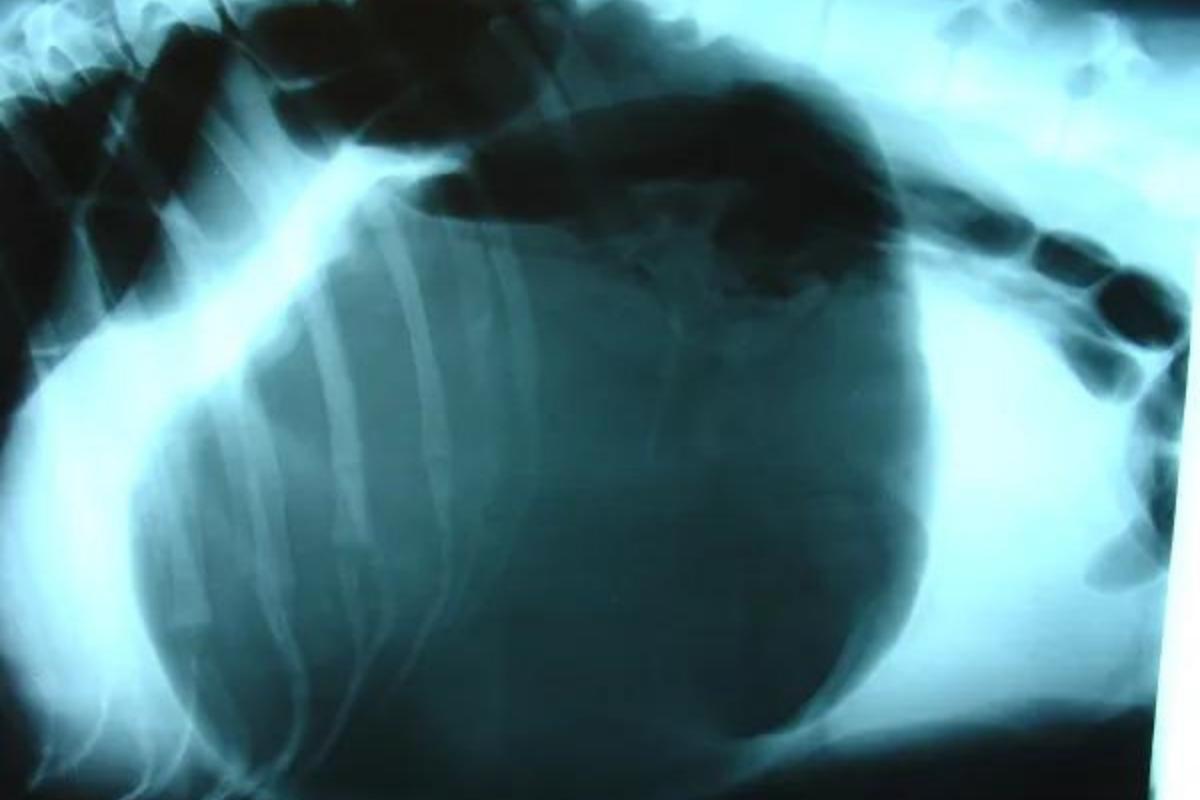

Dilatación/torsión gástrica

La dilatación/torsión gástrica es una patología en la que el estómago de los perros sufre una distensión anormal como consecuencia de la acumulación de gas y líquido. Esta dilatación se sigue de una rotación o torsión del órgano, la cual altera su posición anatómica habitual. Generalmente, estos pacientes presentan:

- Un abdomen muy distendido

- Un fuerte dolor cólico

- Gran nerviosismo

Habitualmente, es una enfermedad que afecta a perros de raza grande y gigante. No obstante, existen razas de menor tamaño que están especialmente predispuestas a sufrir esta patología, como el basset hound o el shar pei.